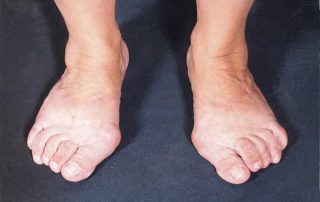

Niewydolność mięśnia piszczelowego tylnego

Schorzenie dotyczy najczęściej kobiet. Wada polega na koślawym ustawieniu stępu, a co za tym idzie obciążaniu przyśrodkowego brzegu stopy. Przodostopie ustawia się w przymusowej supinacji. W dużym nasileniu prowadzi do zwichnięcia kości piętowej do boku.